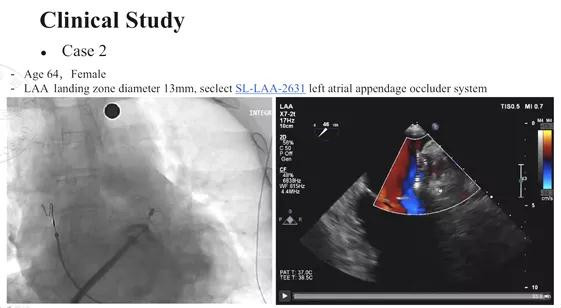

另一例患者为64岁女性,左心耳植入区域的直径为13mm,根据经食道超声以及造影检查的结果,使用的是26-31mm的SeaLA®封堵器。